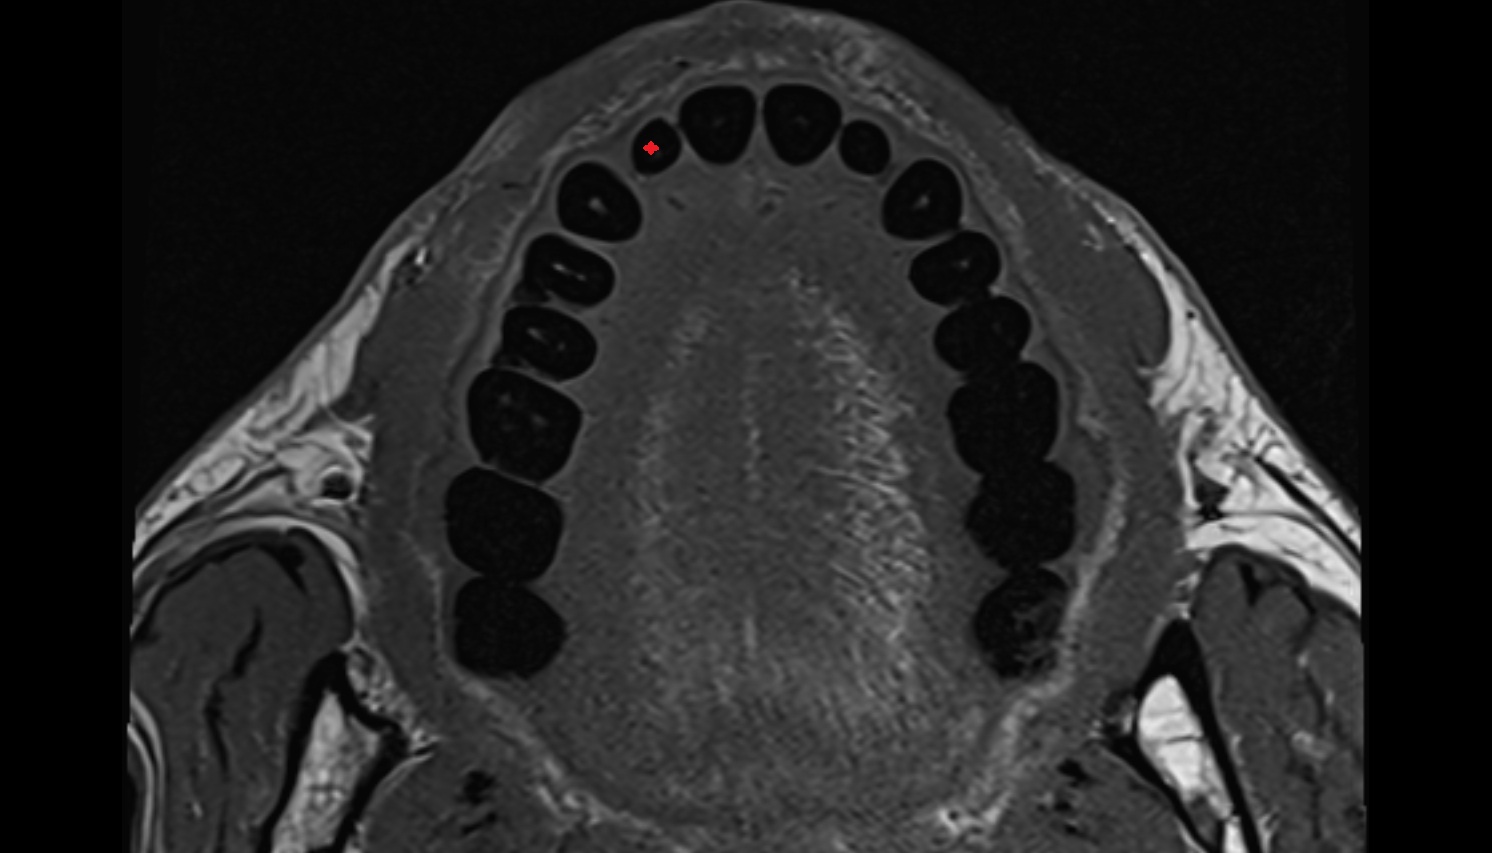

- Central inferior incisor tooth

- Central superior incisor tooth

- Inferior canine tooth

- Lateral inferior incisor tooth

- Lateral superior incisor tooth

- superior canine tooth

- Superior first molar tooth

- Superior first premolar tooth

- Superior second molar tooth

- Superior second premolar tooth

- Superior third molar tooth

- Inferior first premolar tooth

- Inferior second molar tooth

- Inferior second premolar tooth

- Inferior third molar tooth